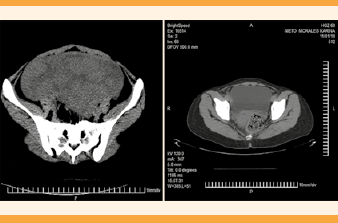

El segundo ultrasonido pélvico reportó: útero en anteflexión con aumento de volumen, bordes regulares definidos, de 16.8 x 7.2 x 13.2 cm; miometrio con ecogenicidad heterogénea a expensas de múltiples imágenes hipoecoicas ovaladas y redondeadas, bien delimitadas, de diferente tamaño y diseminadas en esta zona, de 5.6 x 2.4 cm, 2.6 x 1.2 cm, 1.8 x 1.4 cm, 2.6 x 1.6 cm y 3.2 x 2.1 cm. La cavidad endometrial central, ecogénica y lineal. El ovario derecho se apreció de forma, tamaño y situación normal, de bordes regulares, definidos, de 48 x 27 x 37 mm, con volumen de 24.7 cc, incluido un quiste de 24 x 14 mm. El ovario izquierdo de tamaño y situación normal, de 26 x 19 x 30 mm, volumen de 8.03 cc y parénquima homogéneo. Se informaron múltiples lesiones hipoecoicas diseminadas en el miometrio, de apariencia metastásica, sin relación con imágenes características de miomas. (Figuras 1 y 2) Debido al súbito incremento de tamaño, comparado con el ultrasonido pélvico previo, se solicitó una tomografía pélvica y determinación de marcadores tumorales. Ésta reportó: hígado con aumento de tamaño del lóbulo izquierdo, densidad conservada; útero de 173 x 76 x 125 mm, con perímetro liso; miometrio de aspecto heterogéneo, a expensas de múltiples lesiones ovoides, bien delimitadas, isodensas, con diámetro mayor de 17-80 mm, de localización dispersa, con predominio en la cara anterosuperior, que comprimían y desviaban el endometrio hacia la derecha. Endometrio lineal, de 5 mm, sin adenopatías ni líquido libre en la cavidad abdomino-pélvica. Se identificaron leiomiomas de tipo intramural de medianos y grandes elementos, ovarios sin lesiones visibles y hepatalgia a expensas del lóbulo izquierdo. (Figura 3) La concentración de marcadores tumorales estuvo dentro de los límites de referencia: Ca-125 30.34 u/mL y deshidrogenasa láctica de 265 u/L.

Figura 3 Tomografía computada que evidencia el miometrio de aspecto heterogéneo, a expensas de múltiples lesiones ovoideas, bien delimitadas, isodensas, de localización dispersa, con predominio en la cara anterosuperior.